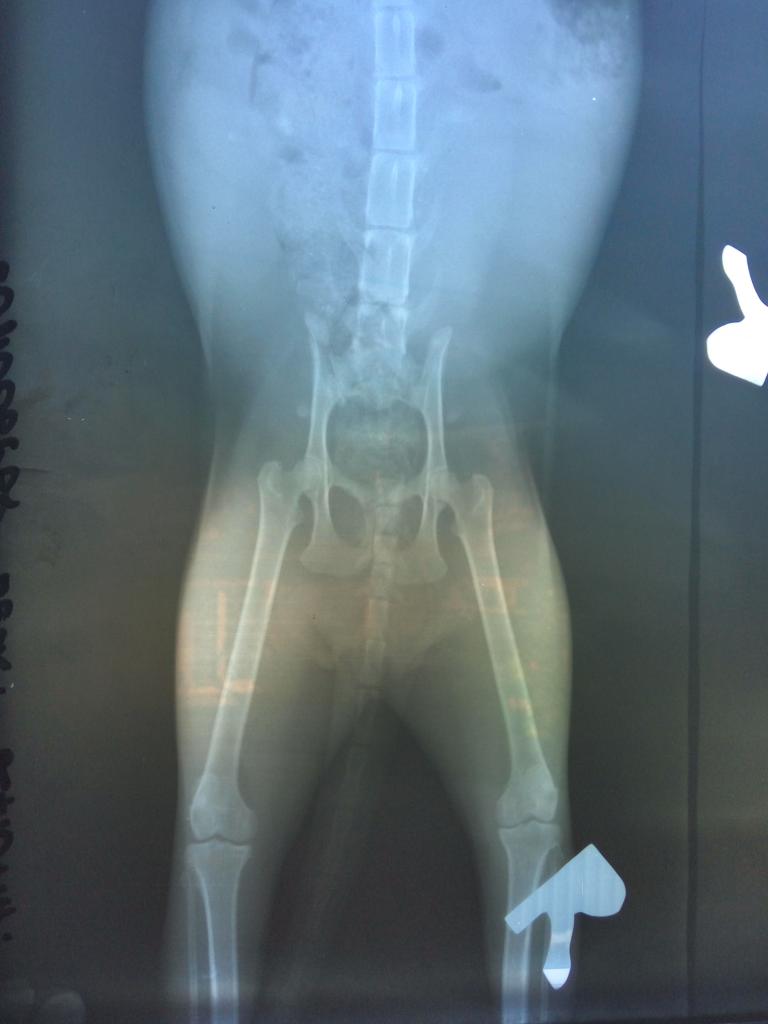

Прибилась ко мне больная кошечка с безжизненно висящим хвостом. Первым делом была осмотрена, напоена, накормлена. На спинке полоска вырванной шерсти, бугорок на копчике и сломанный хвост, задние лапки, к счастью, в порядке Повезли в Красный лис, осмотр и рентген показал перелом хвоста в крестцовой зоне, забитый желудок и прямая кишка, подозрение на мегаколон. Травмы нанесены человеком. Хвостик нужно ампутировать. и стерелизация,есть беременность (2-3 недели), которую нужно прервать,т.к. родить не сможет.